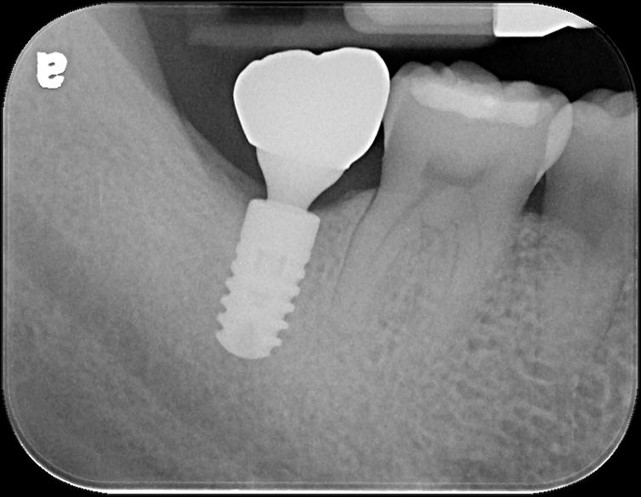

植牙

螺絲固定型假牙

治療後,咬合牙周適應良好

治療後,密合度良好